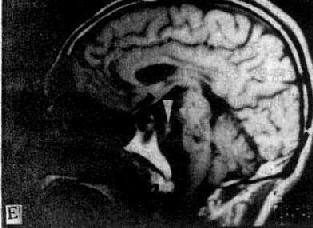

MRI 适宜于观察CT扫描为等密度的亚急性脑内血肿,已如前述。脑梗塞的发现MRI比CT扫描要早,一般起病后6小时MRI即可出现异常。脑干和小脑腔隙性梗塞灶的探测,MRI明显优于CT。脑梗塞灶在T1WI上呈低信号,在T2WI上呈高信号(图5-1-6C、D)。

图5-1-6 MRI扫描SE序列图像

在矢状面(A)和冠状面(B)T1WI可见垂体肿块向鞍上延伸,呈等信号区(→);在横断面T1WI(C)和T2WI(D)上分别可见左枕和右基底节区脑梗塞灶呈低和高信号区(→);在矢状面T1WI(E)和横断面T2WI(F)上,可见基底动脉瘤环形影,其内为低信号和高信号区,高信号区为瘤内血栓形成(→)